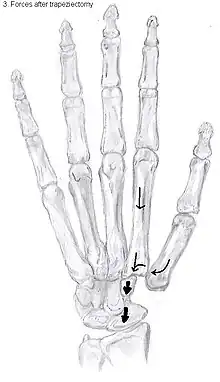

Trapeziectomy

During trapeziectomy,[30] the trapezium bone is removed without any further surgical adjustments. The trapezium bone is removed through an approximately three centimeter long incision along the lateral side of the thumb. To preserve surrounding structures, the trapezium bone is removed "by splitting" it into pieces.

An empty gap is left by the trapeziectomy and the wound is closed with sutures. Despite this gap, no significant changes in function of the thumb are reported.[27] After the surgery, the thumb will be immobilized with a cast.

Trapeziectomy with tendon interposition

Some physicians still believe that it is better to fill the gap left by the trapeziectomy. They assume that filling the gap with a part of a tendon is preferable in terms of function, stability and position of the thumb. This is based on the assumption that interposition can help maintain the space between the metacarpal and the scaphoid, which will improve comfort and capability. Neither of these assumptions is supported by experimental evidence.

Trapeziectomy with ligament reconstruction

Another technique is used to reconstruct the volar beak ligament after trapeziectomy. The rationale is that ligament reconstruction(LR) helps maintain the gap between the metacarpal and the scaphoid, and that a larger gap is associated with greater comfort and capability.[32] Again these possibilities are not supported by experimental evidence.

Trapeziectomy with LRTI

Some physicians believe that combining LR with TI will help maintain gap between the metacarpal and the scaphoid.[33] And that doing so will improve comfort and capability. Keep in mind that these aspects of the rationale are not supported by experimental evidence. The evidence suggests that all of these procedures have comparable long-term results.